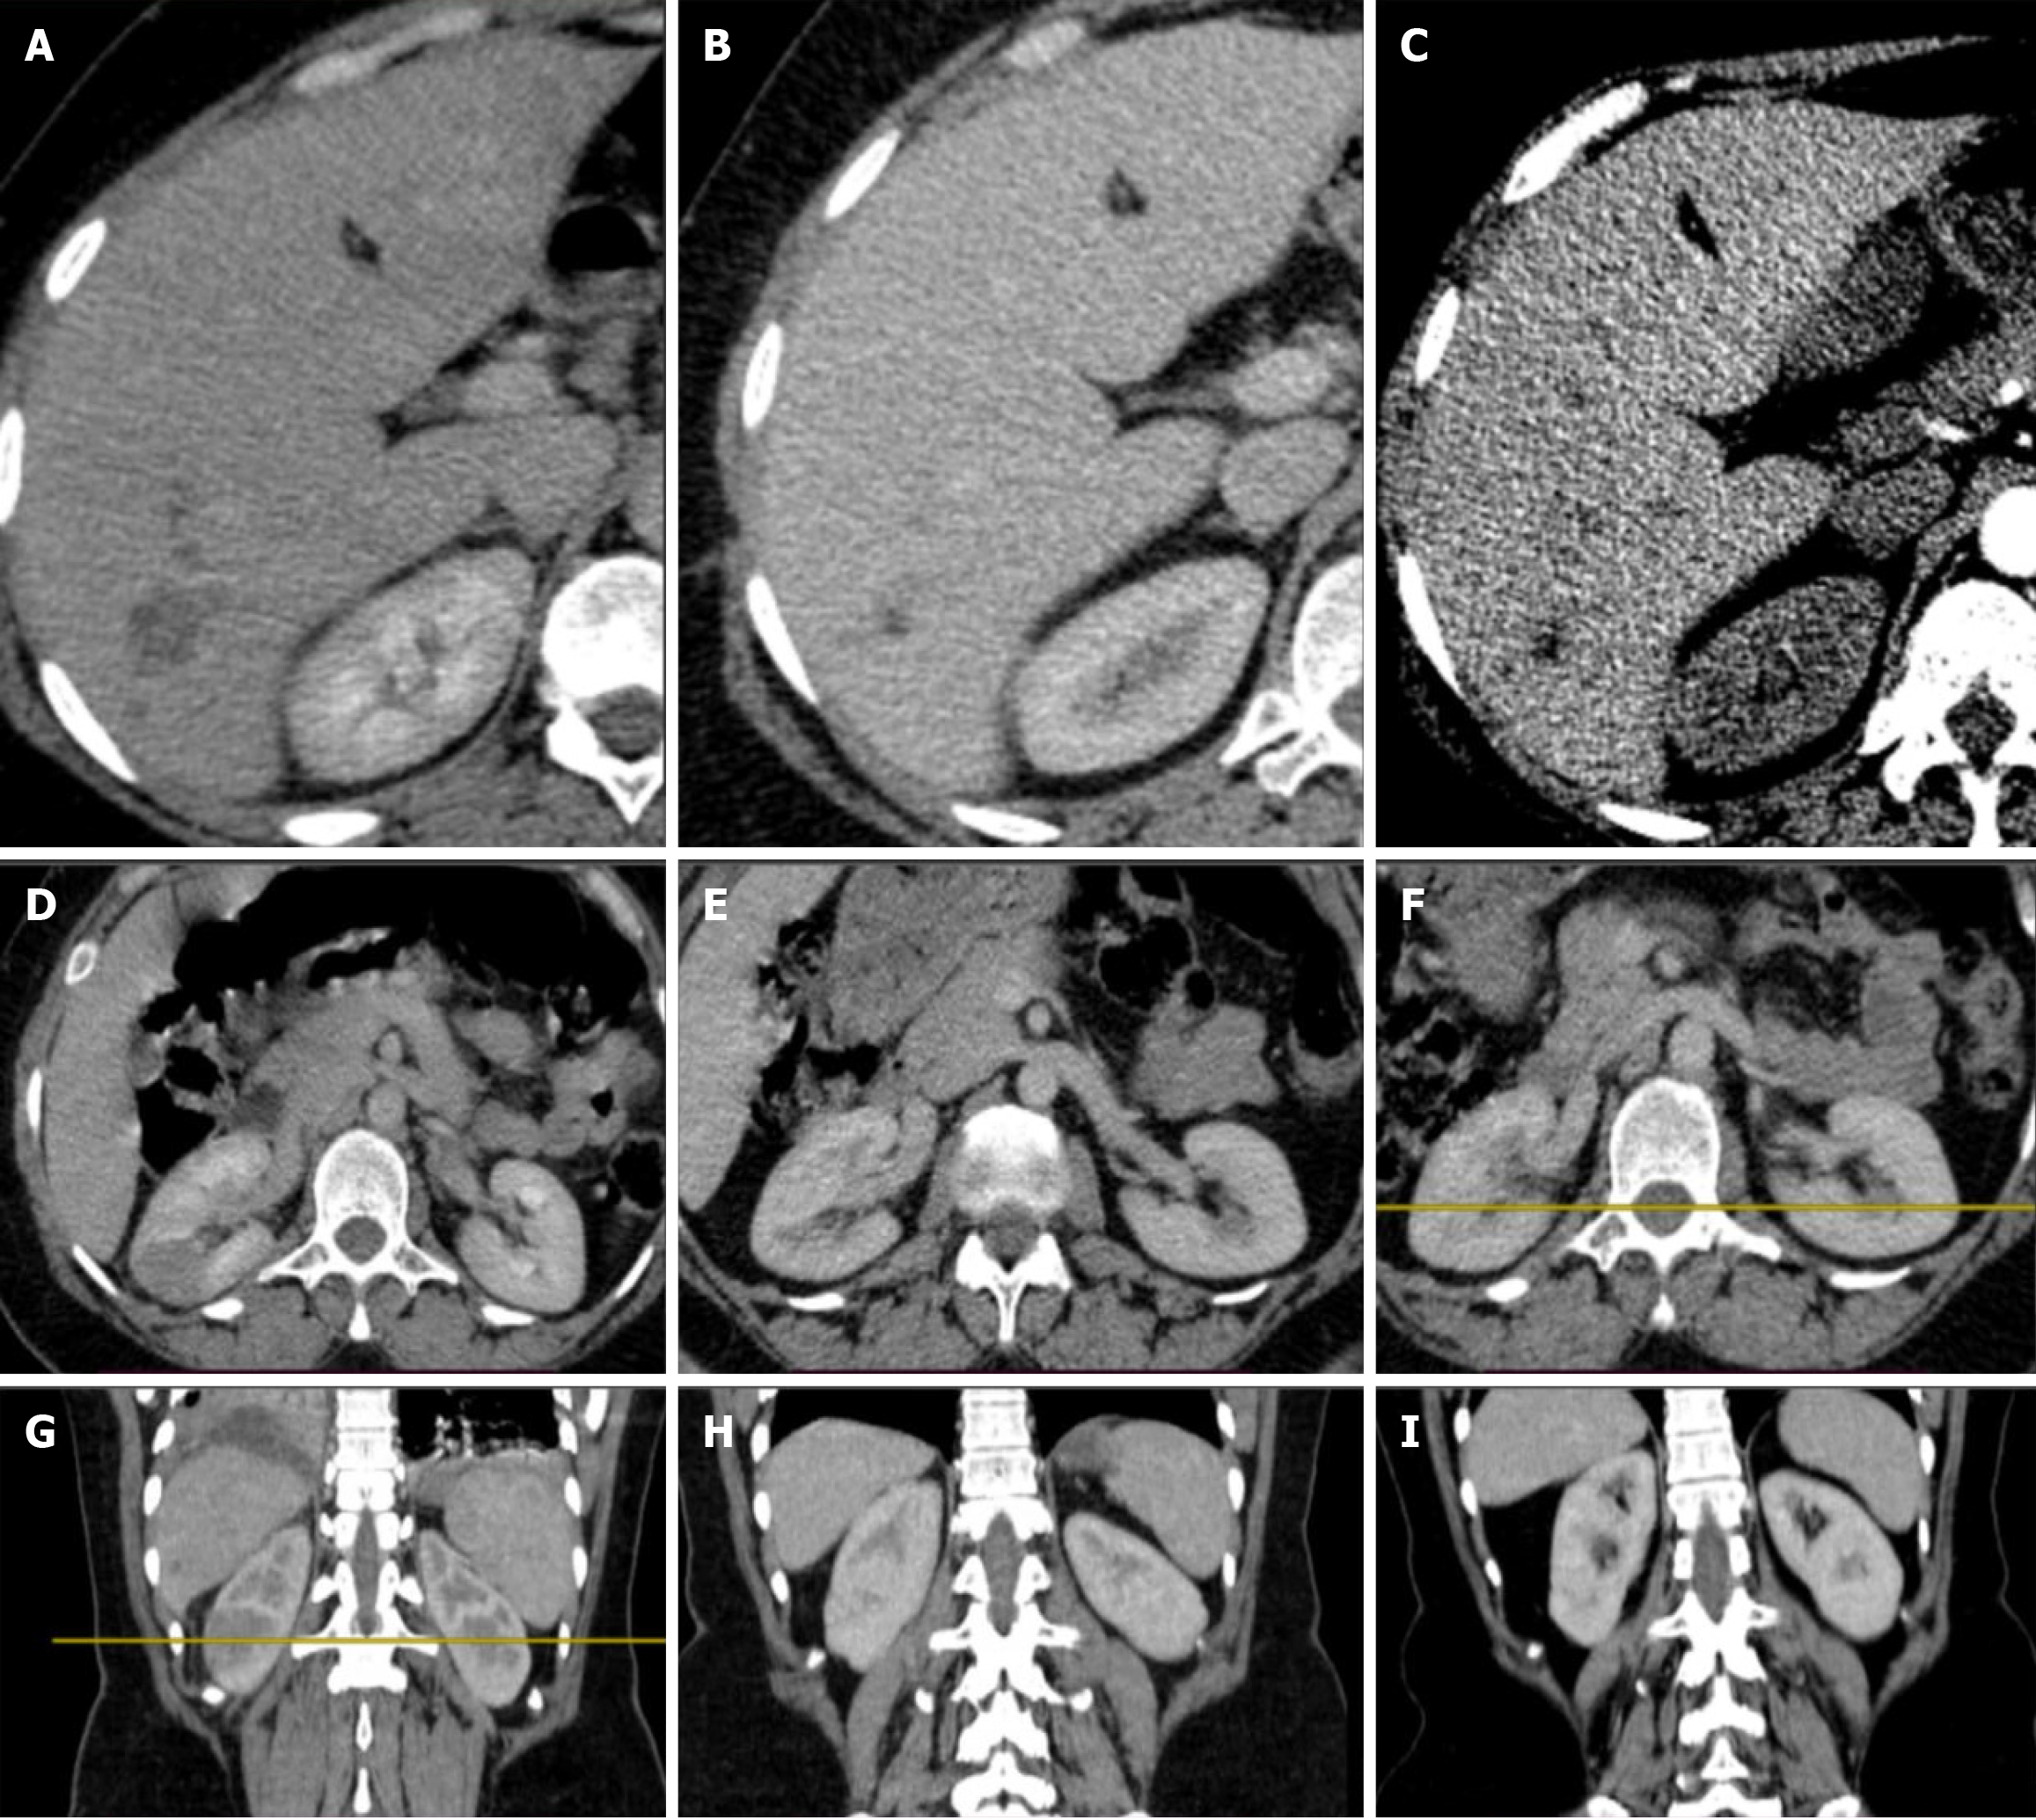

Figure 7 Serial computed tomography imaging depicting radiographic changes with treatment.

A-C: Abdominal computed tomography (CT) images of the liver showing changes with treatment; D-F: Abdominal CT images of the kidneys showing improvement with treatment; G-I: Abdominal CT scans demonstrating the progression of hepatic and renal lesions throughout the clinical course, from initial presentation to post-treatment follow-up.